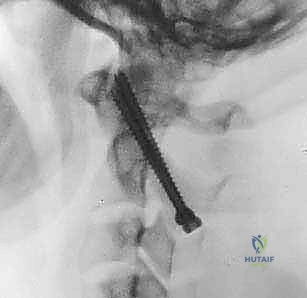

تُعرف التقنية الأكثر شيوعاً وفعالية اليوم باسم تقنية هارمز/جويل (Harms/Goel Technique)، والتي تتضمن وضع مسامير في الكتل المفصلية للفقرة C1 ومسامير في عنيقة أو جزء (Pars) الفقرة C2، ثم ربطها بقضبان معدنية. يتطلب هذا الإجراء مهارة جراحية فائقة، استخدام الميكروسكوب الجراحي، والتوجيه بالأشعة السينية داخل غرفة العمليات.

الخطوة 6: تركيب القضبان واستعادة المحاذاة (Reduction)

بعد وضع المسامير الأربعة بنجاح، يتم تقييم وضعية الفقرات. إذا كانت C1 منزلقة للأمام، يتم استخدام أدوات خاصة لسحبها للخلف واستعادة المحاذاة الطبيعية مع C2 (عملية تُسمى Reduction). بمجرد تحقيق الوضعية المثالية، يتم قص قضيبين من التيتانيوم بالطول المناسب وتثبيتهما بقوة في رؤوس المسامير. هذا يخلق "سقالة" معدنية صلبة تمنع أي حركة بين الفقرتين.

الخطوة 7: التصوير الشعاعي داخل العمليات

طوال الإجراء، وخاصة بعد تركيب المسامير والقضبان، يتم استخدام جهاز الأشعة السينية المحمول (C-arm